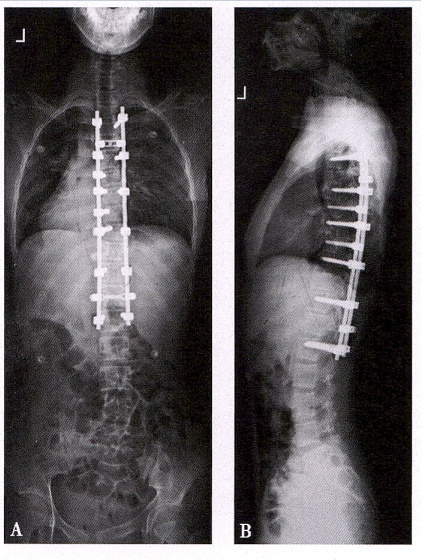

手术治疗

适用于Cobb 角>40°、病情快速进展(每年增加 5° 以上)、严重影响心肺功能或出现神经症状的患者。目的是通过脊柱融合、内固定等方式矫正畸形,阻止病情发展,保护脏器和脊髓功能。手术具有一定创伤性,术后需进行康复训练,帮助恢复脊柱活动能力。

脊柱侧弯手术X线图像